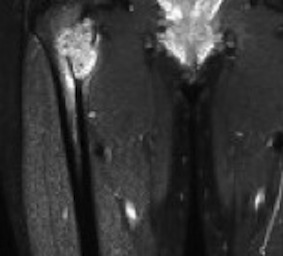

MRI

Low signal intensity of T1 / high signal intensity on T2

- intramedullary extent

Significant soft tissue mass with significant edema

Ewing proximal femur

Ewing's humerus